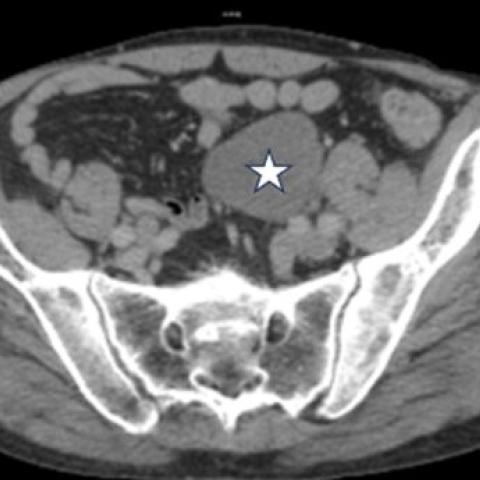

CT扫描示多个非典型位置的转移灶。这些转移灶在影像学上呈现出相似的特征,表现为低密度改变。转移灶的分布广泛,涉及心脏内部(右心室和左心室)、纵隔(后纵隔)、腹腔、左侧前腹壁以及右侧阴囊。

盆腔左侧与相邻肠袢和同侧髂血管接触的低密度肿块(白色星号)。